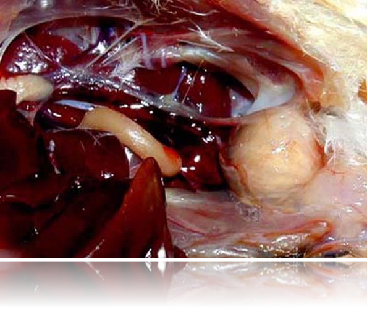

法氏囊肿大